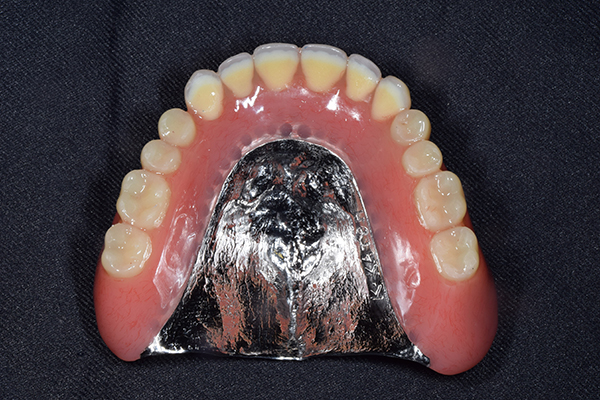

金属を使用して、薄く違和感が少ない入れ歯が完成しました。 また、見た目にも気を使い、バネが見えにくい様な構造にしました。

義歯は下顎で、しっかり噛めること、違和感の少ないものという希望があったため、なるべく入れ歯を薄く作成するために金属をしようした義歯とした。

また、見た目もあまり義歯が目立たない様に、バネの部分を見えにくいように作成した。